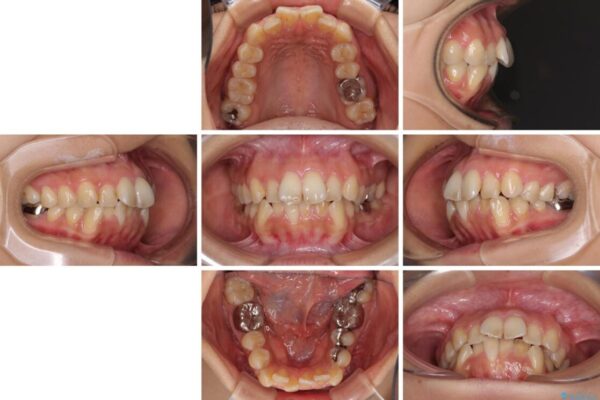

前歯のデコボコと上顎の前突感による口の閉じにくさを気にして来院された患者様です。

目立たない装置を希望されたので、上顎が裏側装置のハーフリンガルを選択し、上下左右の小臼歯(計4歯)を抜歯して矯正治療を行うこととしました。

治療前

• デコボコと口元の突出感 ハーフリンガルでの抜歯矯正 治療前画像